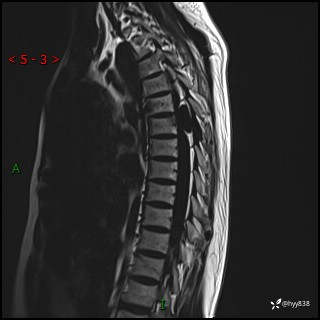

胸椎MRI平扫(sag T1WI+T2WI)